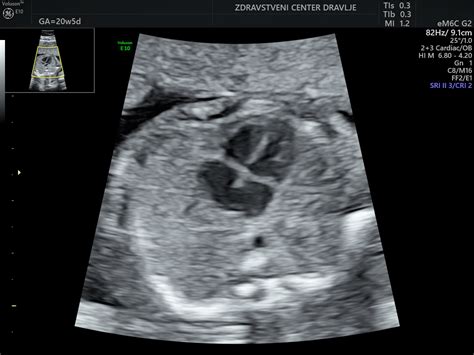

Zastoj v rasti ploda pomeni, da je ocenjena velikost plodu manjša, kot bi jo pričakovali glede na gestacijsko starost. Rast plodu spremljamo z ultrazvokom (UZ), pri čemer ultrazvočne meritve vnašamo v krivulje rasti, ki nam omogočajo sledenje razvoju. Kot je pojasnila ginekologinja in porodničarka Nataša Tul Mandič, obstajajo za otroke vseh starosti, vključno z dojenčki, že desetletja krivulje rasti, ki omogočajo oceno, ali je posameznik primerno velik, premajhen (zaostal v rasti) ali celo prevelik. Za Slovence imamo že dolgo časa lastne krivulje rasti za novorojenčke, ki nam takoj po rojstvu omogočajo oceno, ali je novorojenček primerno velik. Krivulje rasti so narejene tako, da je pet ali 10 odstotkov zdravih posameznikov vedno pod spodnjo mejo. Če ugotovimo, da je novorojenček manjši, kot smo pričakovali glede na višino nosečnosti, v kateri se je rodil, najprej pogledamo, kako veliki so njegovi starši, in nato ocenimo, ali je zares zaostal v rasti. Medicina plodu (fetalna medicina) se je začela razvijati v 70. in 80. letih 20. stoletja, zato v zadnjih desetletjih spremljamo tudi rast plodu.

Vzroki pri plodu: Bolezni plodu, ki povzročajo zastoj rasti, so lahko kromosomske ali genetske bolezni. Del teh bolezni lahko odkrijemo z UZ že pred rojstvom. Presejalni test za zgodnje odkrivanje kromosomskih in genetskih nepravilnosti je UZ med 11. in 14. tednom nosečnosti z oceno nuhalne svetline v kombinaciji s hormonskimi testi. Nekatere znake bolezni pri plodu lahko odkrijemo tudi na rednem pregledu plodu med 20. in 24. tednom nosečnosti ali kasneje. Žal pa je veliko genetskih bolezni (ki so sicer redke) težko ugotoviti pred rojstvom.

Ob ugotovitvi, da plod zaostaja v rasti (včasih je potrebnih več meritev v razmaku od dveh do štirih tednov, da opredelimo zastoj rasti), vedno ocenimo še količino plodovnice, izgled posteljice, telesne strukture plodu (morfologija plodu), pretoke skozi različne žile ter zdravstveno stanje nosečnice. Šele na podlagi analize vseh dejavnikov, ki lahko vplivajo na rast plodu, in opažanj se odločimo, kako bomo ukrepali. Včasih odvzamemo vzorec plodovnice, da izključimo kromosomske bolezni plodu, včasih zdravimo nosečnico, iščemo okužbe, včasih se odločimo za takojšen porod ali pa samo za podrobnejše spremljanje rasti plodu. Kako bomo ukrepali, je odvisno od višine nosečnosti in spremljajočih ugotovitev; enotnega recepta ni.